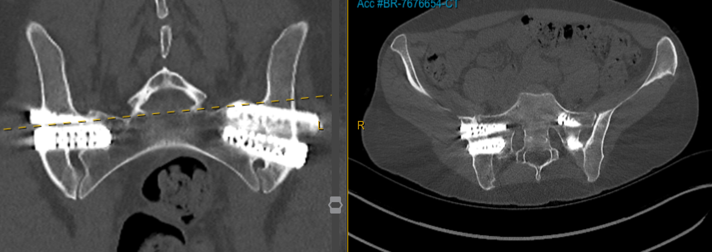

For carefully selected patients with persistent SI joint dysfunction, robotic fusion may provide a definitive stabilization option after conservative and minimally invasive treatments have been exhausted.

A 21-year-old active gymnast with hypermobility, several years of back pain, and severe SIJ tenderness underwent multiple prior treatments before robotic sacroiliac joint fusion led to good pain improvement and return to reasonable normal activity.

A 38-year-old psychologist with hypermobile EDS had severe back pain and instability over several years, short-term relief from prolotherapy, and a largely normal lumbar MRI despite major symptoms.